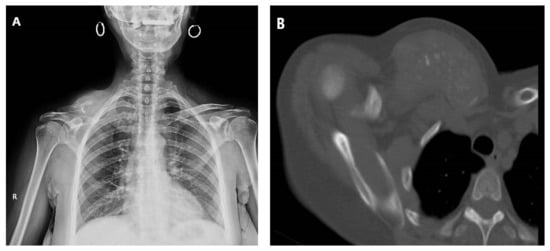

Figure 4.

(A) Preoperative CT scan of a 55-year-old patient diagnosed with a manubrial tumor. (B) A large resection of the tumor was performed, within oncological limits. (C) After resection, rigid reconstruction was performed using a Stratos titanium bar on the upper side of the operative field. The medial part of the clavicle is shown. (D) Next, a polypropylene mesh was utilized in the left upper corner. The incision used for sectioning of the deltoid tuberosity insertion of the left pectoralis major is shown. (E) For soft-tissue reconstruction, a pectoralis major flap was harvested (main pedicle at the tip of the clamp). (F) The intraoperative aspect with the pectoralis major flap was secured over the polypropylene mesh.

Rigid chest wall reconstruction can be performed using both biological and synthetic materials. Biological materials have the advantage of biocompatibility but are less resistant over time, increase the operating time, and can result in donor site complications. On the other hand, synthetic materials have an increased resistance but might lead to infection, extensive fibrosis, migration, or shredding/rupture. Osteosynthesis systems, such as Stratos or MatrixRIB fixation, have proven utility for rigid reconstruction (Figure 4). Customized titanium implants manufactured using 3D prototyping technology, combined with a myocutaneous pedicled flap, have been proven safe for use in extended anterior chest wall resection [49,50].